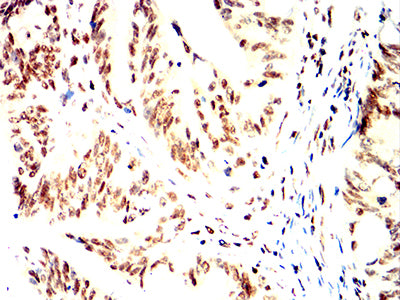

- Immunohistochemical analysis of paraffin-embedded human liver tissues using RFA2 mouse mAb with DAB staining.

- Immunohistochemical analysis of paraffin-embedded human bladder cancer tissues using RFA2 mouse mAb with DAB staining.

- Immunohistochemical analysis of paraffin-embedded human esophageal cancer tissues using RFA2 mouse mAb with DAB staining.

- Immunohistochemical analysis of paraffin-embedded human rectum cancer tissues using RFA2 mouse mAb with DAB staining.